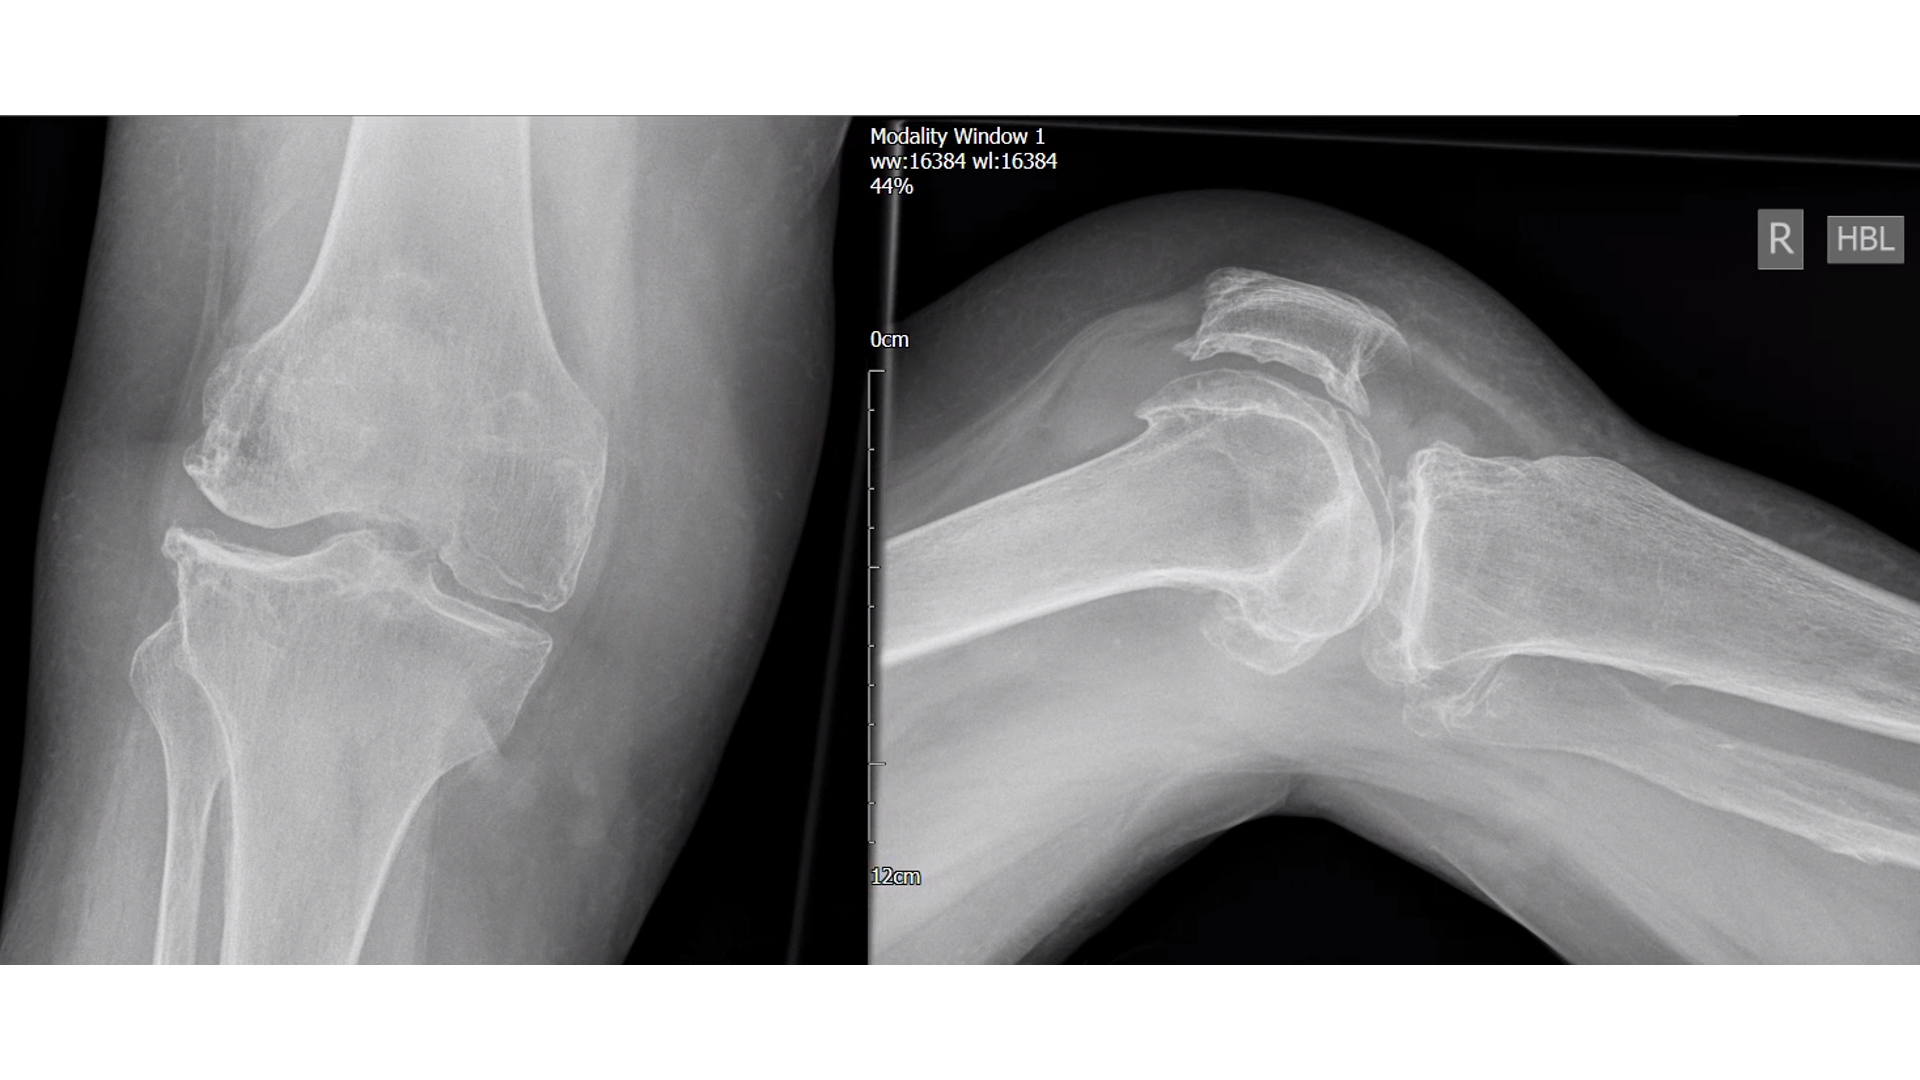

The x-ray film shows clear signs of osteoarthritis (OA) throughout the knee.

Joint space narrowing

Osteophytes (bone spurs)

We talked through her x-ray films, the extent of the OA and that there was still some joint space ..a key part of the story.